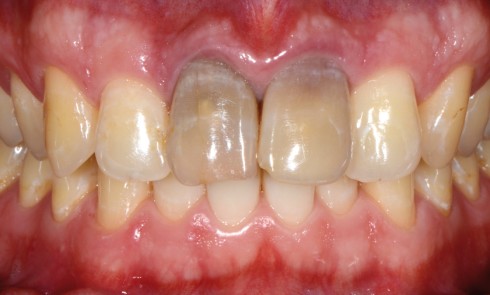

Article réservé à nos abonnés Eclaircissement et consolidation d’une dent dépulpée antérieure dyschromiée

L’éclaircissement interne est une technique simple qui permet de résoudre le problème de la couleur dans un grand nombre de...